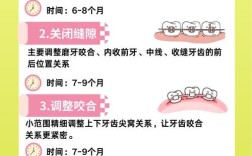

(图片来源网络,侵删)

(图片来源网络,侵删)- 环境: 确保治疗区域光线充足,视野清晰。